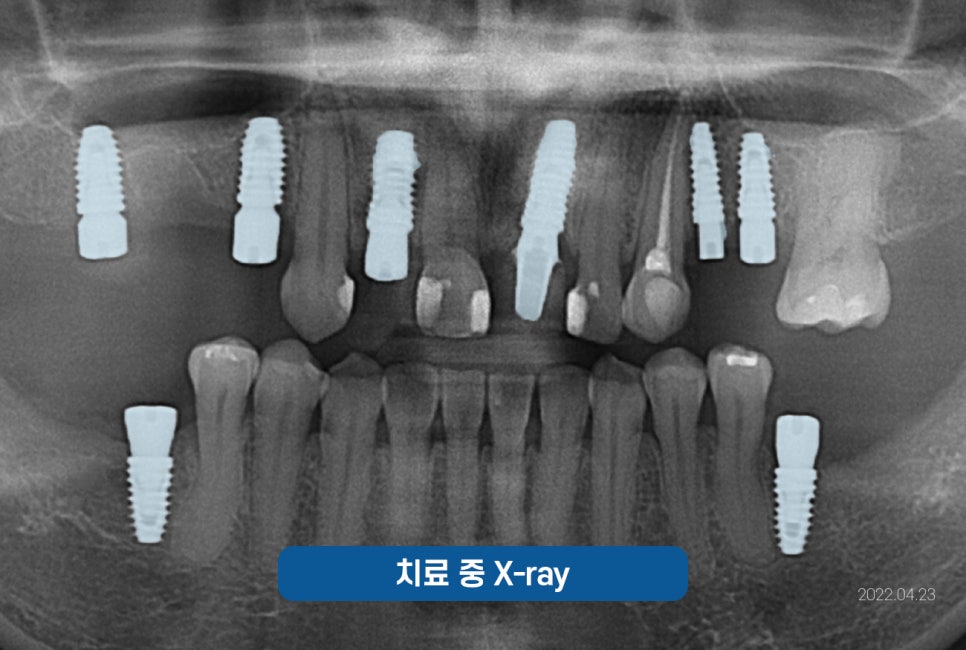

진료 받으신 분의 케이스를

한번 살펴보겠습니다.

*이해를 돕기 위해 동의 후 사용한 증례로

진료의 결과는 개인에 따라 달라질 수 있으니

주치의와 충분히 의논한 후 결정하시기 바랍니다.

잠원역치과 임플란트 케이스

치아를 상실하셔서

잠원역치과 서울센텀에

임플란트 수술을

받으러 오신 분의 케이스인데요.

치과의 두려움으로

방문을 미루시다가

다수의 치아를 잃어

임플란트를 해야할 것 같아

방문해 주셨습니다.

하지만 비용에 대한 걱정으로

고민이 많으셨는데요.

걱정을 덜어드리기 위해

만 65세 이상이셔서

저희가 먼저 보험 임플란트를

권해드렸었고, 비교적 적은 비용으로

진료를 받게 되셨습니다.

상의를 한 후, CT촬영에 들어갔고

한번 더 체크를 한 후

수술 준비에 들어갔습니다.

심한 풍치로 흔들림이 심하고

예후가 안 좋은데

평소 불편한 점이 없었냐고 여쭤보니

잇몸이 좋지 않아 잦은 출혈이 보였고

흔들림이 심해 앞니로 베어먹기에 힘들어

고민이 많으셨다고 하셨습니다.

그래서 치아를 최대한 살리는 방향으로

고민을 해 보았으나,

이미 수명을 다한 치아로

안타깝지만 발치를 하기로 결정내렸습니다.

결론적으로 앞니 치아

하나를 발치하였으며

치아가 상실된 자리에

임플란트를 식립해드렸습니다.

그럼, 식립한 사진을 함께 볼까요?

🔽

임플란트는 바로

치아 머리가 올라가는 게 아닌

골유착을 유도하기 위해

뿌리만 식립하고 3개월 정도

기다린 뒤

뼈와 임플란트가 잘 붙었는지

기계로 측정 후

잘 붙었다고 판단되면

본을 떠서 보철을 올려드리고 있어요.^^